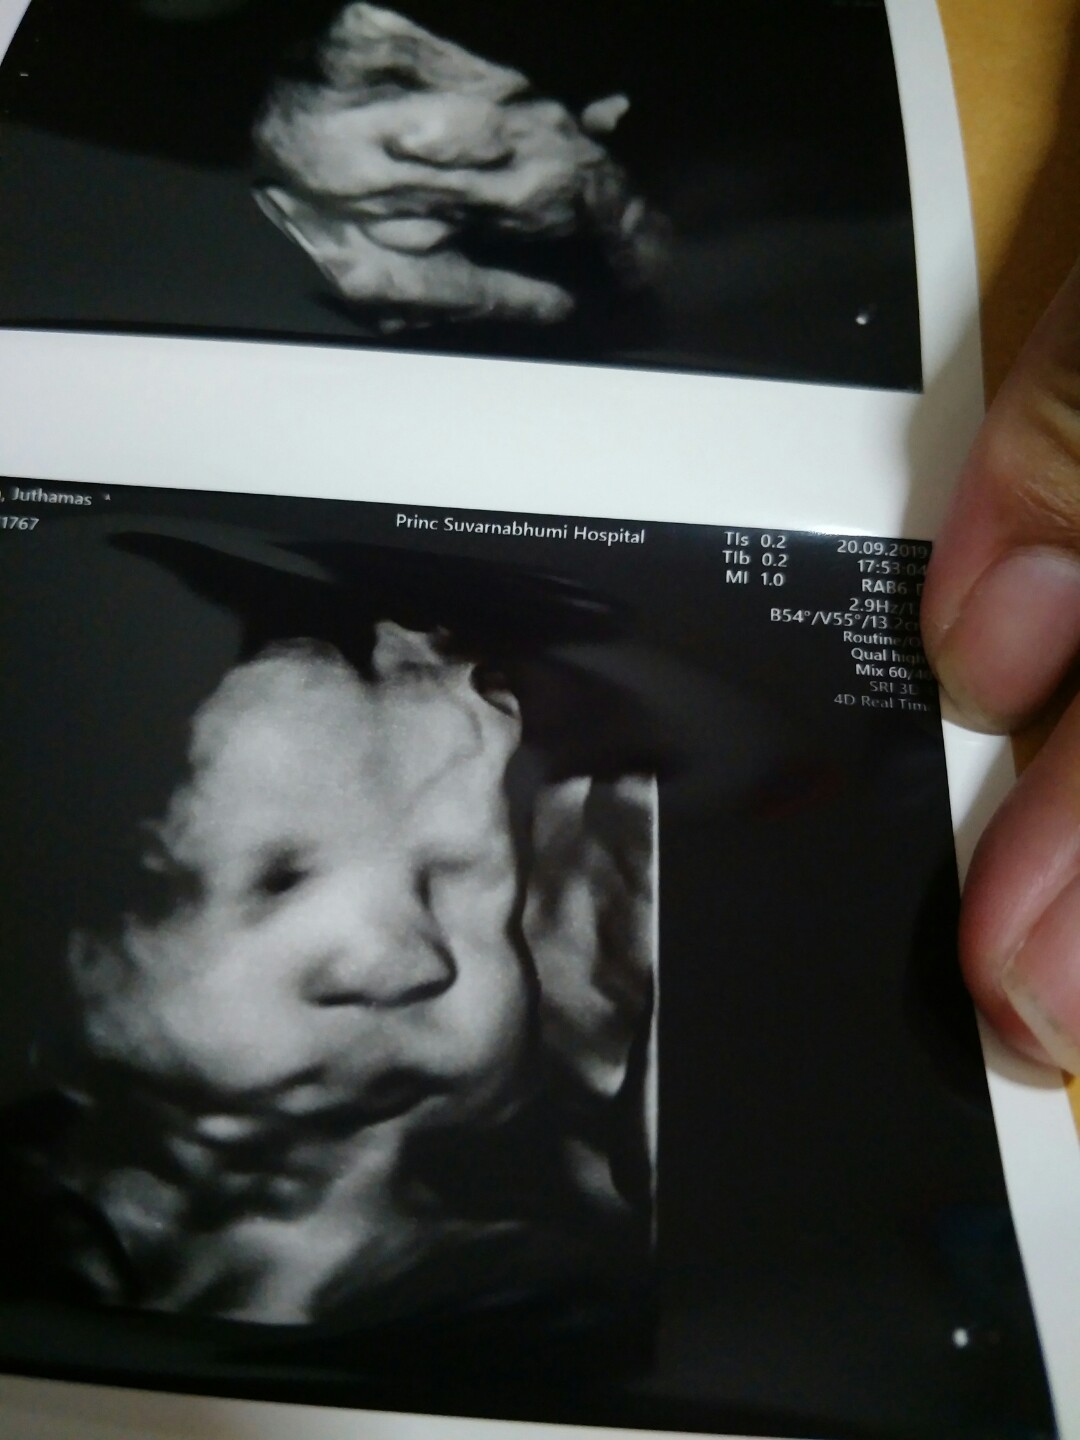

เอาเด็กชายปากคว่ำ เดือน พย. มาอวดจ้า

อายุครรถ์ 32วีค5วัน ผมหนัก 2,100 แล้วครับ ขอดูเด็กเดือน พย. น่ารักๆหน่อยครับ ผมไม่ชอบเลยเวลาคุณหมอซาวด์ หน้าจะบึ้งหน่อยๆ55555